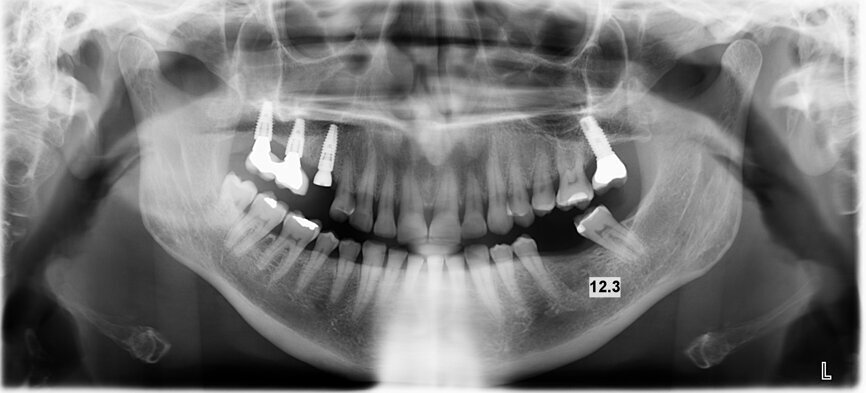

A BLT implant (Regular Neck, Roxolid, ⌀ 4.1 × 12.0 mm) was placed in position #15. As the insertion torque value and Implant Stability Quotient (ISQ) level were not optimal for immediate loading, a delayed protocol with a healing cap was selected.

Two months later, a panoramic radiograph showed an excellent situation for the BLT implant and correct healing of position #36 (Fig. 1). Following a chairside protocol, it was decided to load implant #15 and provide an implant treatment with immediate loading in position #36 on the same day. This involved the design of two screw-retained crowns with the TRIOS Design Studio software, and their production in n!ce material on the C series milling unit.

Under local anaesthesia, a flapless implant surgery technique was performed in position #36. Owing to the quality of the bone, staged drilling with continuous saline irrigation was performed in order to obtain a proper, safe insertion torque (Figs. 2–7). One implant (BLT, Regular Neck, Roxolid, ⌀ 4.8 × 10.0 mm) was placed, and a torque of 42 N cm was applied (Figs. 8–11).

The ISQ level was determined with the Osstell unit. After connecting a Type 54 SmartPeg, a score of 82 was obtained (Fig. 12). The decision to employ an immediate loading protocol has to take account of the surgeon’s personal experience and skills, the insertion torque value, the ISQ levels and the medical and dental characteristics of the patient. In this case, all these parameters were evaluated as excellent, and the immediate loading protocol was selected.